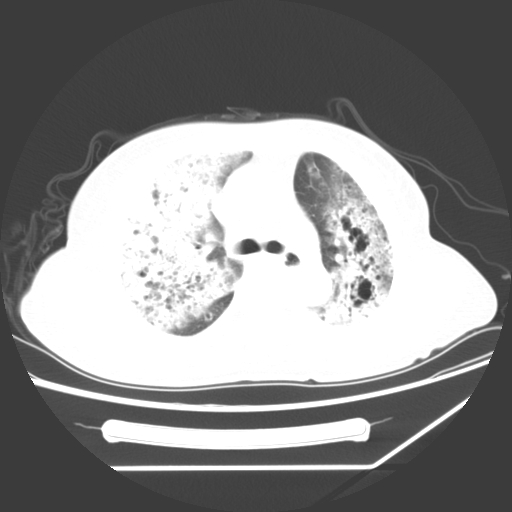

标题: CT25393:病人45岁,咳嗽,吐黄痰带血丝,发热,胸闷月余 [打印本页]

标题: CT25393:病人45岁,咳嗽,吐黄痰带血丝,发热,胸闷月余

1、左肺中央型肺癌并双肺弥漫性转移   2、双肺部感染    3、肺大泡     4、左侧胸腔积液

双侧肺弥漫性病变,可见“空泡征”及“蜂窝征”,考虑肺泡癌可能性大,左侧胸腔积液,考虑胸膜受累可能!

1)不排除肺泡癌可能。2)左侧胸腔积液。